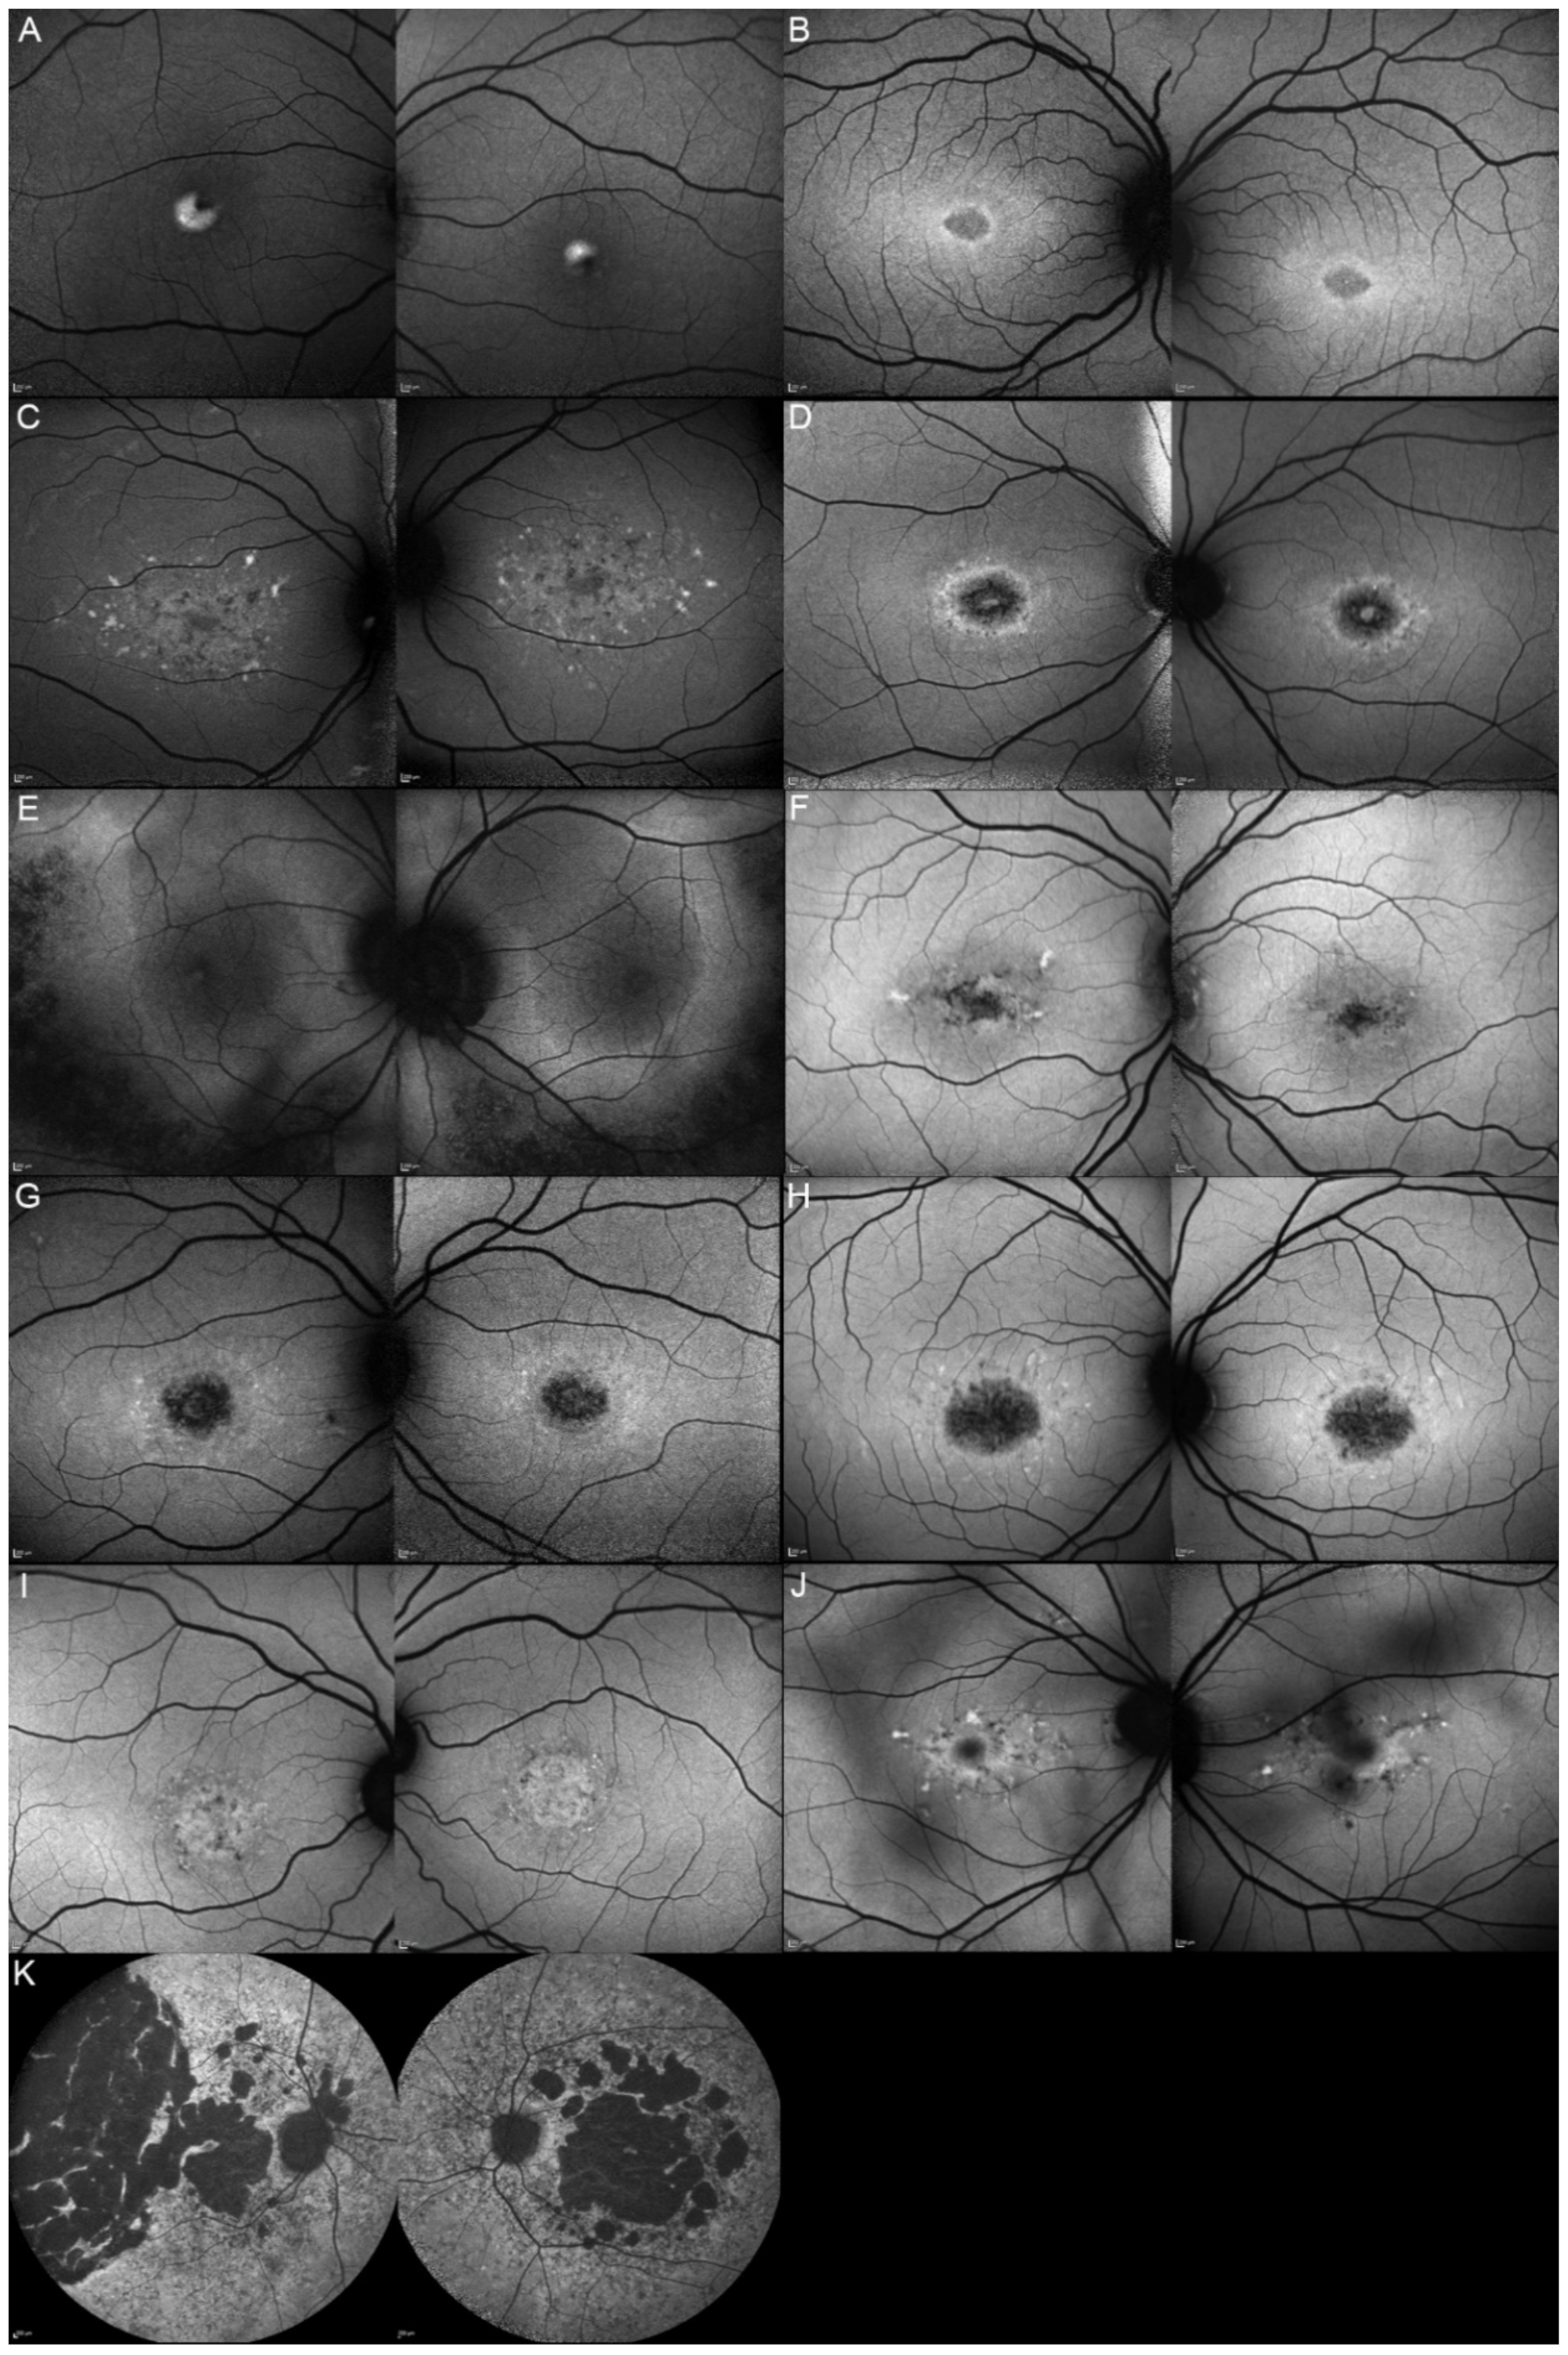

| Patient | Gene | Age | Sex | FAF | OCT |

|---|---|---|---|---|---|

| 1, II.2 | ABCA4 | 53 | F | Foveal HPAF | Subretinal hyperreflective deposits |

| 2, II.1 | ABCA4 | 18 | F | Central HOAF; concentric ring of HPAF | Central EZ disruption with gap; ONL atrophy |

| 3, II.2 | ABCA4 | 18 | F | Foveal HOAF; central mottled pattern of HPAF and HOAF flecks | Central EZ loss; central ONL atrophy |

| 4, II.2 | ABCA4 | 27 | F | Foveal HPAF; parafoveal HOAF; paramacular HPAF | Central EZ loss; central ONL atrophy |

| 5, II.2 | ABCA4 | 69 | F | Mid-peripheral mottled HOAF | Mid-peripheral ONL atrophy, lamellar macular hole (OD) |

| 6, II.2 | ABCA4 | 53 | F | Foveal HOAF; central mottled pattern of HPAF and HOAF flecks | Central EZ disruption with gap (OS) and loss (OD); central ONL atrophy |

| 7, II.1 | ABCA4 | 19 | F | Central HOAF; HPAF flecks | Central EZ loss; central ONL atrophy |

| 8, III.2 | ABCA4 | 30 | M | Central HOAF; HPAF flecks | NA |

| 9, II.2 | ABCA4 | 44 | F | Central mottled pattern of HPAF and HOAF flecks | Central EZ loss; central ONL atrophy |

| 10, I.2 | ABCA4 | 51 | F | Foveal HOAF; central mottled pattern of HPAF and HOAF flecks | Perifoveal EZ loss; perifoveal ONL atrophy; loss of the foveal depression |

| 11, III.1 | ABCA4 | 53 | M | Extended central and peripheral HOAF; panretinal diffuse mottled pattern of HPAF and HOAF flecks | ONL atrophy; peripheral choroidal atrophy; RPE atrophy; subretinal hyperreflective deposits |

| 12, II.2 | ELOVL4 | 37 | F | Central HOAF; concentric ring of HPAF | Central EZ loss; central ONL atrophy and RPE atrophy |

| 13, II.1 | ELOVL4 | 46 | F | Multifocal areolar parafoveal HOAF; mottled pattern of HPAF and HOAF flecks; perimacular to mid-peripheral HPAF flecks | Perimacular EZ loss; perimacular ONL atrophy; subretinal hyperreflective deposits |

| 13, III.2 | ELOVL4 | 19 | F | No special features | Subfoveal hyperreflective deposits (OD) |

| 13, III.1 | ELOVL4 | 21 | M | NA | No special features |

| 13, I.1 | ELOVL4 | 82 | M | Areolar HOAF; paracentral mottled pattern of HPAF and HOAF flecks | ONL thinning; perimacular localised EZ loss (OS) |

| 14, II.4 | ELOVL4 | 48 | M | Central mottled pattern of HPAF and HOAF flecks | Central EZ loss; central ONL atrophy; perimacular subretinal hyperreflective deposits |

| 15, II.3 | ELOVL4 | 34 | M | Subfoveal HOAF; concentric ring of HPAF | Central EZ disruption with gap; central ONL atrophy |

| 16, III.2 | ELOVL4 | 28 | F | NA | NA |

| 17, II.1 | PRPH2 | 51 | F | Butterfly pattern of HPAF and HOAF flecks; paramacular to mid-peripheral HPAF flecks | Irregular EZ thickening |

| 18, II.2 | PRPH2 | 69 | M | Subfoveal HOAF (OS); butterfly pattern of HPAF and HOAF flecks; paramacular to mid-peripheral HPAF flecks | Central EZ loss (OS); central ONL atrophy (OS); localised ONL thinning (OD) |

| 19, III.2 | PRPH2 | 39 | F | Central areolar HOAF; disseminated nummular HPAF | Extended retinal atrophy |